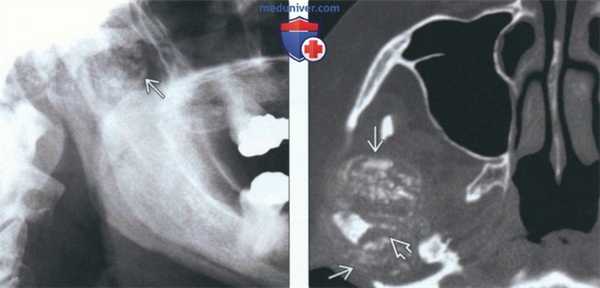

(Слева) На рентгенограмме нижней челюсти в боковой проекции визуализируется крупное объемное образование с диффузным обызвествлением, представляющее собой отложения КПФД в ВНЧС. Из-за наложения сторон невозможно сказать точно, где находится образование - справа или слева.

(Справа) На аксиальной КТ в костном окне у этою же пациента можно оценить размеры хорошо отграниченного объемного образования спереди и сзади от мыщелка. С внутренней стороны мыщелка визуализируется крупный рентгенонегативный дефект (эрозия).